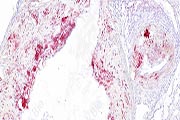

陕西依科生物技术服务有限公司致力于生物科研试剂的研发、销售及相关技术服务。从事的领域包括石蜡包埋、切片、HE染色、冰冻切片、各种特殊染色、免疫染色、Tunel染色和其他相关病理技术服务。同时,公司还建立了独立实验室,开展Real-time PCR和Western blot等分子生物学实...